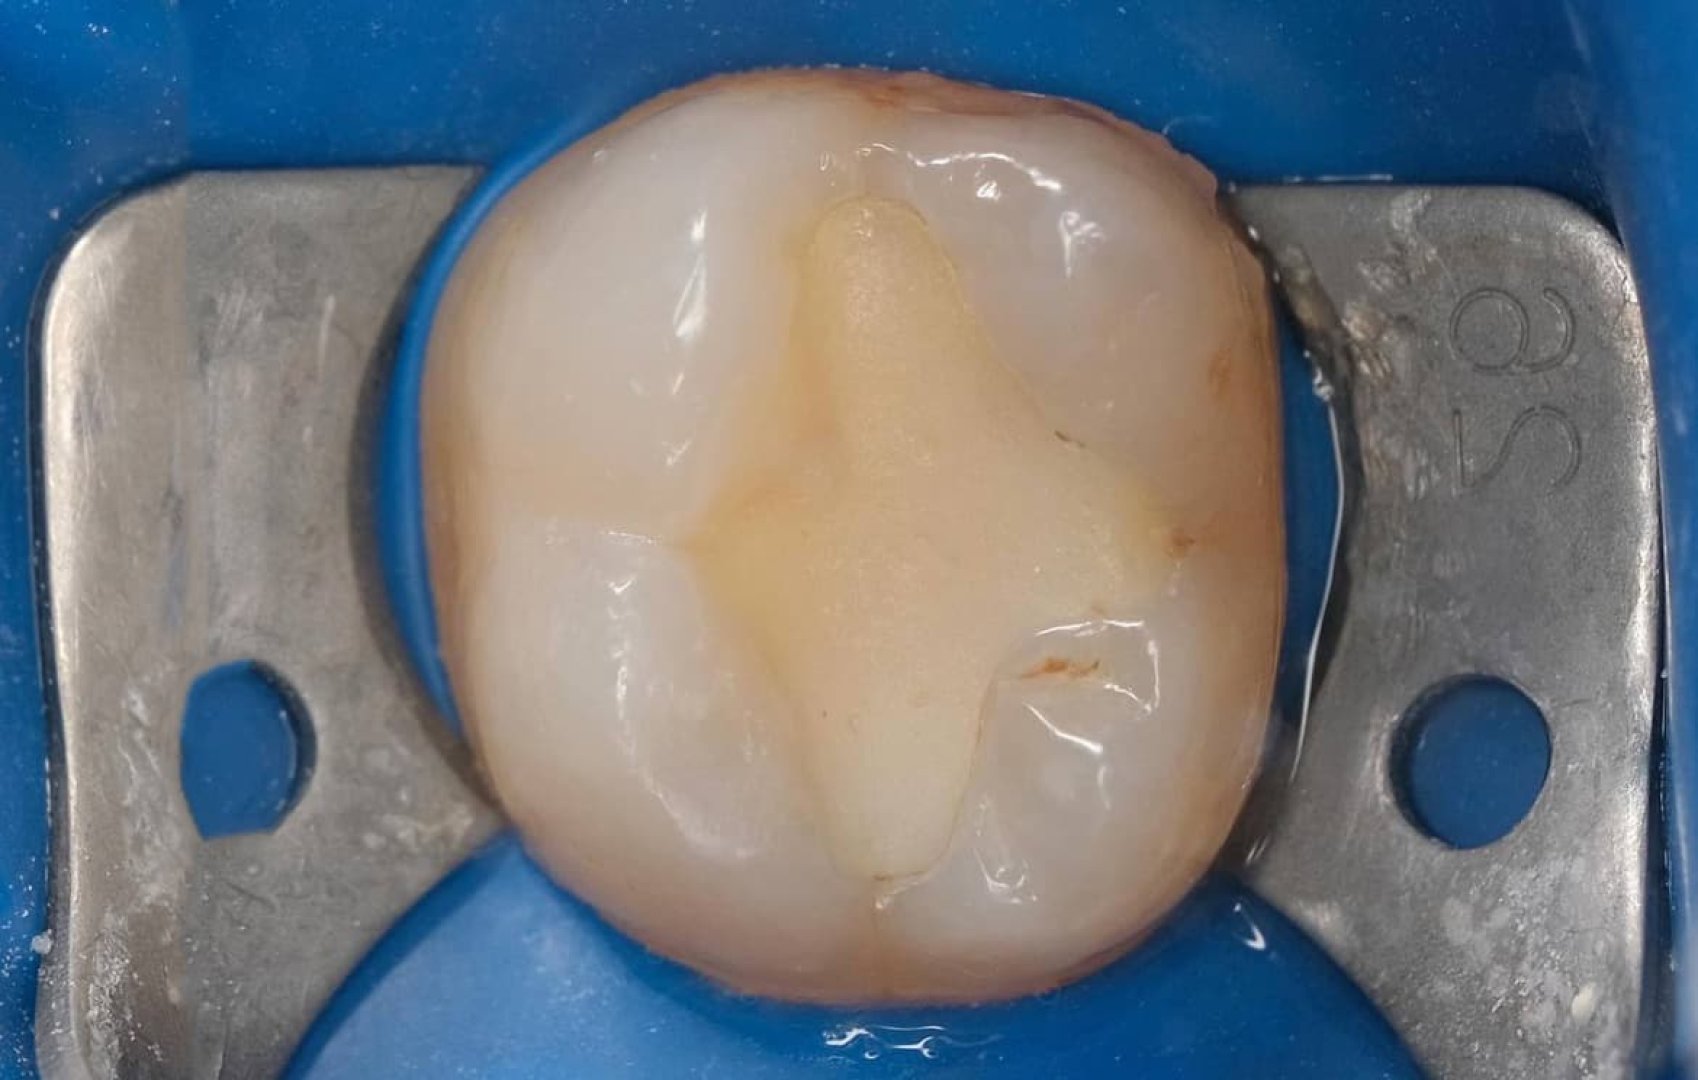

Замена старой пломбы 4.7

Пациент обратился со старой пломбой, установленной на изолирующую прокладку. Такие конструкции со временем становятся уязвимыми.